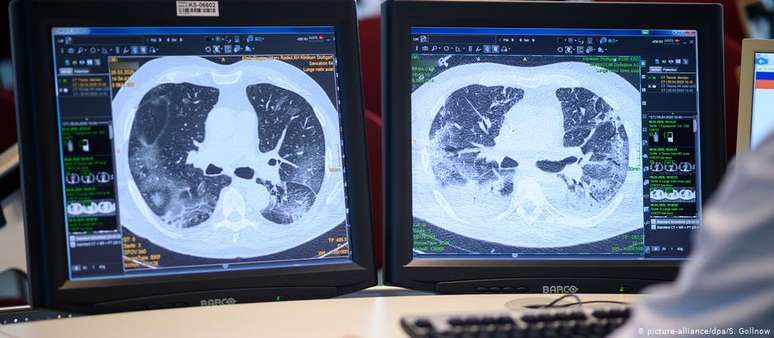

Muitos pacientes apresentam como sequela uma redução da capacidade pulmonar

No decorrer da covid-19, os pulmões são fortemente atacados, mas o dano nem sempre para por aí: muitos pacientes apresentam como sequela uma redução da capacidade pulmonar. Cientistas chineses detectaram um turvamento semelhante a vidro leitoso nas tomografias de doentes recuperados, sugerindo a ocorrência de lesões permanentes.

Pesquisa-se no momento se esses pacientes desenvolveram fibrose pulmonar, uma formação patológica de tecido cicatricial. Ao enrijecer o tecido dos pulmões, ela pode dificultar o transporte de oxigênio para os vasos sanguíneos, provocando em respiração superficial e rápida, e tosse seca e irritável. O resultado é uma queda do desempenho físico, tornando difíceis até mesmo atividades quotidianas.

A fibrose pulmonar é irreversível, já que as cicatrizes no órgão não retrocedem, porém seu progresso pode ser desacelerado ou mesmo sustado, se ela é detectada a tempo.